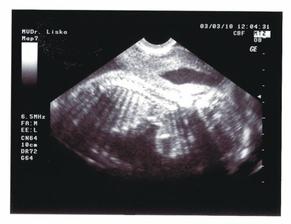

02.03.2010 (20.tt) - Genetický ultrazvuk:máme podrobně prozkoumané miminko, vše je v pořádku, pouze zjištěna mírná dilatace ledvinných pánviček cca 5 mm, dostali jsme doporučení na kontrolní ultrazvuk za měsíc.

03.03.2010 (20.tt) - Na vlastní žádost další ultrazvuk u jiného Dr., abychom dostali mimi na videu - máme úžasný zážitek a ještě úžasnější památku na celý život!